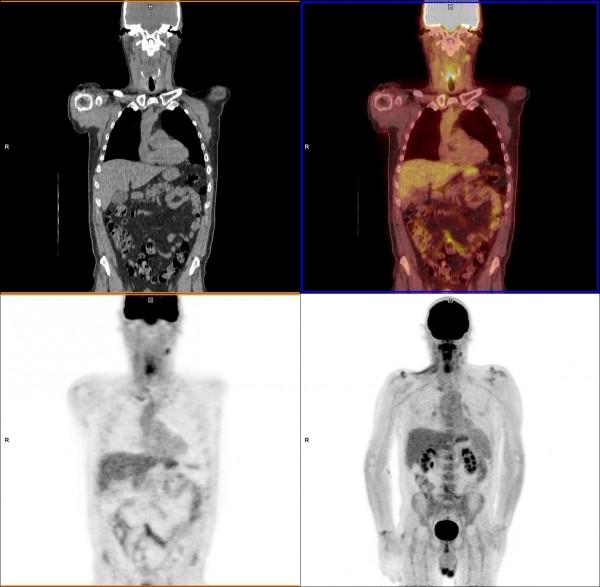

June 14, 2021 — Positron emission tomography (PET) using a 68Ga-labeled fibroblast activation protein inhibitor (FAPI) ...